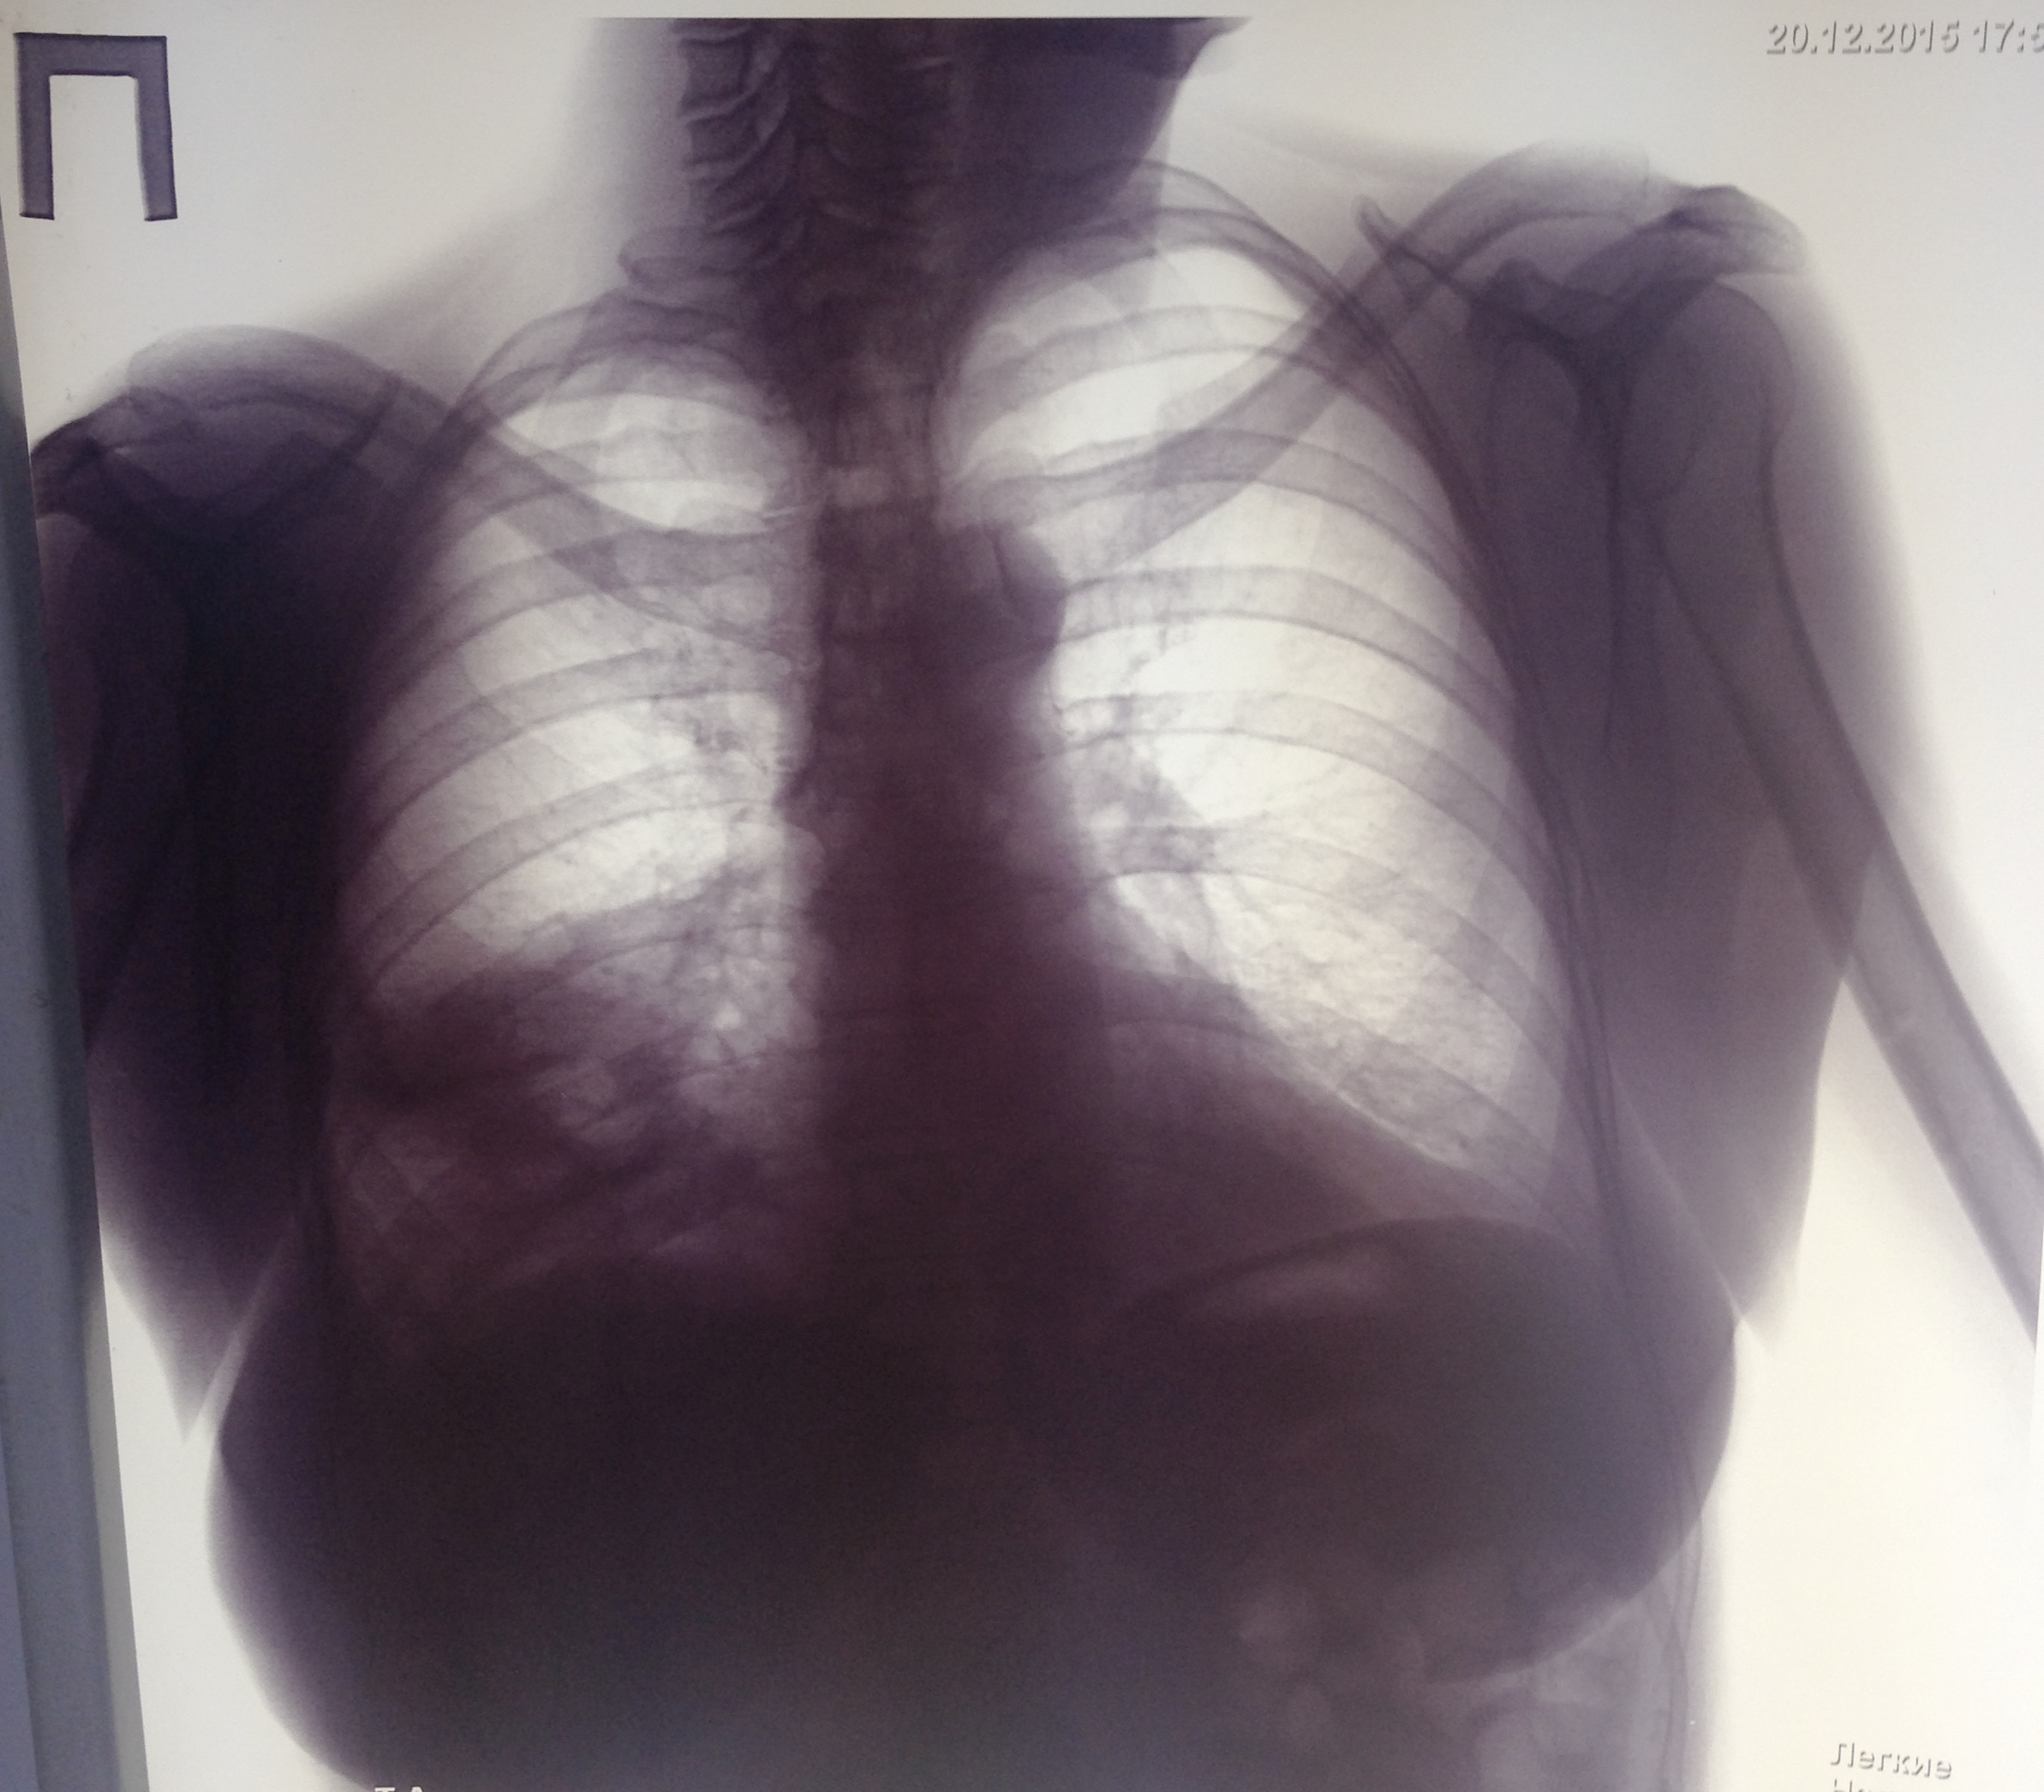

Среднедолевая пневмония. Слева легкого нет.

Обсуждалось в Госпитале Ослабенных Сердец